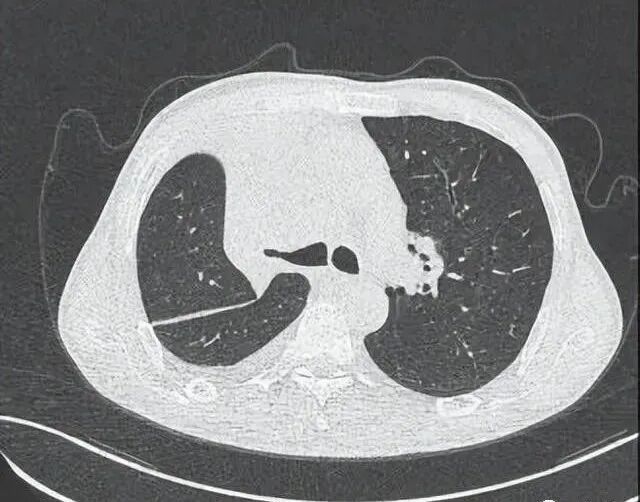

患者,男,58岁。病史非常简单,上腹部间断不适半月。但患者的吸烟史很长,吸烟40多年,每天2包烟,除此之外,患者无其他不良嗜好。患者父母其余兄弟姐妹4人均身体健康,无肿瘤病史。

患者先做了肿瘤标志物,有三项略增高,CA125明显增高,这与生殖系统肿瘤有关;CA125轻度增高,与炎症、积液有关。神经元特异性烯醇化酶(NSE),在小细胞肺癌(SCLC)患者血清NSE明显增高,神经内分泌肿瘤NSE也会明显升高,少数非小细胞肺癌(NSCLC)、甲状腺髓样癌、嗜铬细胞瘤、转移性精原细胞癌、黑色素瘤、胰腺内分泌瘤等也会明显升高,本例只略升高一点,不能根据这项结果就定成肿瘤患者。细胞角蛋白19片段是NSCLC的首选标志物,一般比较高,本例只略升高一点,不能根据这项结果就定成肺癌患者。

再看患者的腹部B超,发现了肝脏多个占位病变,B超没有定性,但根据经验,肝脏内病变可能是转移性病变。